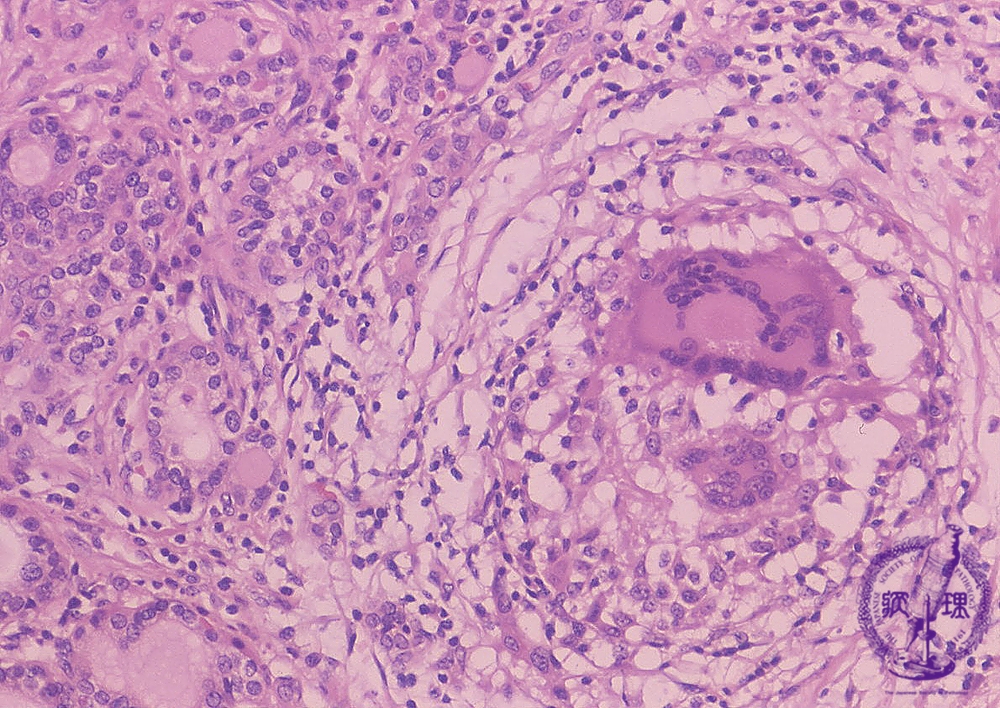

- どうしても診断が付かない場合、炎症の強い部分に甲状腺穿刺細胞診を行い、免疫細胞の多核巨細胞(中等度出現)/類上皮細胞(多数出現)と、好中球(急性炎症の白血球)の浸潤を証明。次項の組織生検(コア生検)で分かるように、多核巨細胞/類上皮細胞は、それ程、数が多くないので、(筆者の経験では)穿刺細胞診をしても検出できない事が多いです。

- 最終手段は組織生検(コア生検)。

甲状腺穿刺細胞診でも亜急性甲状腺炎の診断が付かない場合、あるいは癌性リンパ管炎を否定できない場合、組織生検(コア生検)になります。写真は、病理コア画像[日本病理学会(Japanese Society of Pathology) 教育委員会編集]より引用したものです。